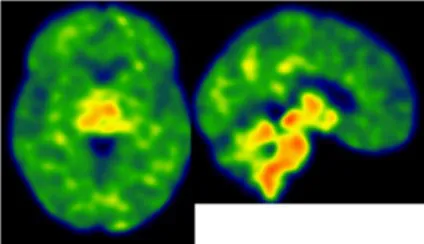

| Clinical findings | CSF and APOE | SWI and T1-weighted MRI scans | Proposition of ongoing neuroinflammatory processes |

| Case 21: a 59 y.o. woman with early onset symptoms and familial history of AD. At screening, she had 23/30 MMSE and impairment on episodic memory, executive functions, processing speed and categorical verbal fluency tests. Three lobar microbleeds, WMH (Fazekas’s score of 3/9) and moderate cortical atrophy were observed on MRI. | Aβ42: 462 P-tau: 140 T-tau: 768 APOE E3/E4 TSPO MAB | ![]() | ![]() Low cortical neuroinflammation compared to the cerebellar cortex. |

All fourth patients are right-handed. TSPO PET imaging showed SUVR relative to the cerebellar cortex and is represented in standard space in the same slice and intensity scale, whereas MRI scans are shown in native space. Cerebrospinal fluid AD biomarker values were abnormal for the four patients (see the method section for details).

Aβ42, amyloid-β 42; AD, Alzheimer’s disease; APOE, apolipoprotein E; CAA, cerebral amyloid angiopathy; CSF, cerebrospinal fluid; MMS, mini-mental state examination; MRI, magnetic resonance imaging, P-tau, phosphorylated tau; SWI, susceptibility-weighted imaging; T-tau, total-tau; TSPO, translocator protein; WB, whole brain; WMH, white matter hyperintensities.